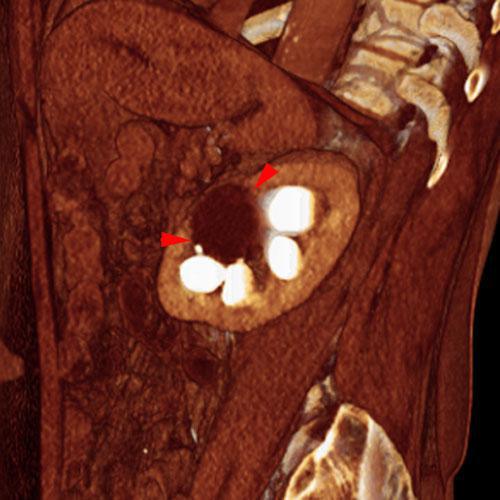

Quiste renal simple